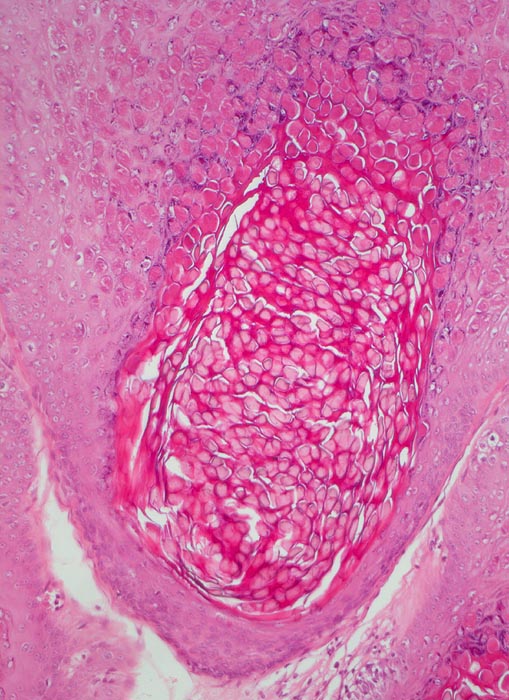

PathoPic ID 5107 - Molluscum contagiosum

Molluscum contagiosum

Haut, Anus

Haut

Kugelige eosinophile intrazytoplasmatische Einschlüsse sind vor allem in Zellen des $o{qy8042178Stratum granulosum} Stratum granulosum und des

Stratum corneum erkennbar.

Perianal kleine linear angeordnete Hautpapeln.

Histologie

100